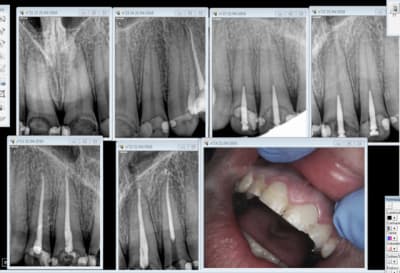

docgentil

04/05/2016 à 18h13

Le Screw du jour.

Ce qui m'attriste le plus c'est que le patient a 25 ans.

Sc33 bczylk - Eugenol